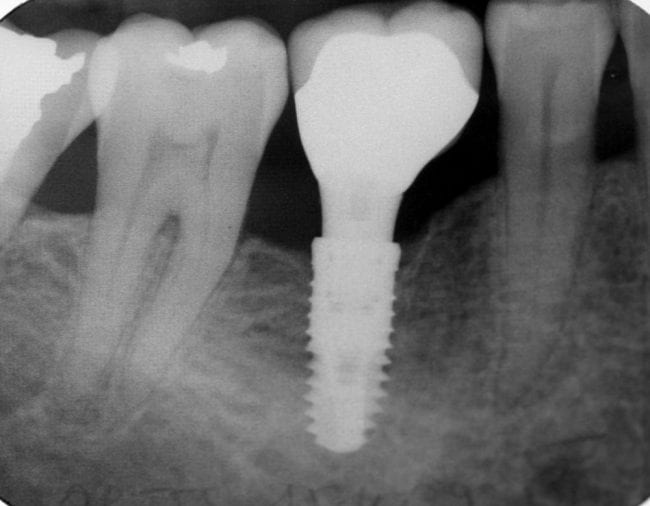

Dental implants are a popular and effective way to replace missing teeth and are designed to blend in with your other teeth. They are an excellent long-term option for restoring your smile. In fact, the development and use of implants is one of the biggest advances in dentistry in the past 40 years. Dental implants are made up of titanium and other materials that are compatible with the human body. They are posts that are surgically placed in the upper or lower jaw, where they function as a sturdy anchor for replacement teeth.

- First, the dentist surgically places the implant into the jawbone. Your dentist may recommend a diet of soft foods, cold foods and warm soup during the healing process.

- Next, the bone around the implant heals in a process called osseointegration. What makes an implant so strong is that the bone actually grows around it and holds it in place. Osseointegration means “combines with the bone” and takes time. Some patients might need to wait until the implant is completely integrated, up to several months, before replacement teeth can be attached to the implant. Other patients can have the implants and replacement teeth placed all in one visit.

- Finally, it’s time for the placement of the artificial tooth/teeth. For a single tooth implant, your dentist will customize a new tooth for you, called a dental crown. The crown will be based on size, shape, color and fit, and will be designed to blend in with your other teeth. If you are replacing more than a single tooth, custom-made bridges or dentures will be made to fit your mouth and your implants. (Note: The replacement teeth usually take some time to make. In the meantime, your dentist may give you a temporary crown, bridge or denture to help you eat and speak normally until the permanent replacement is ready.)